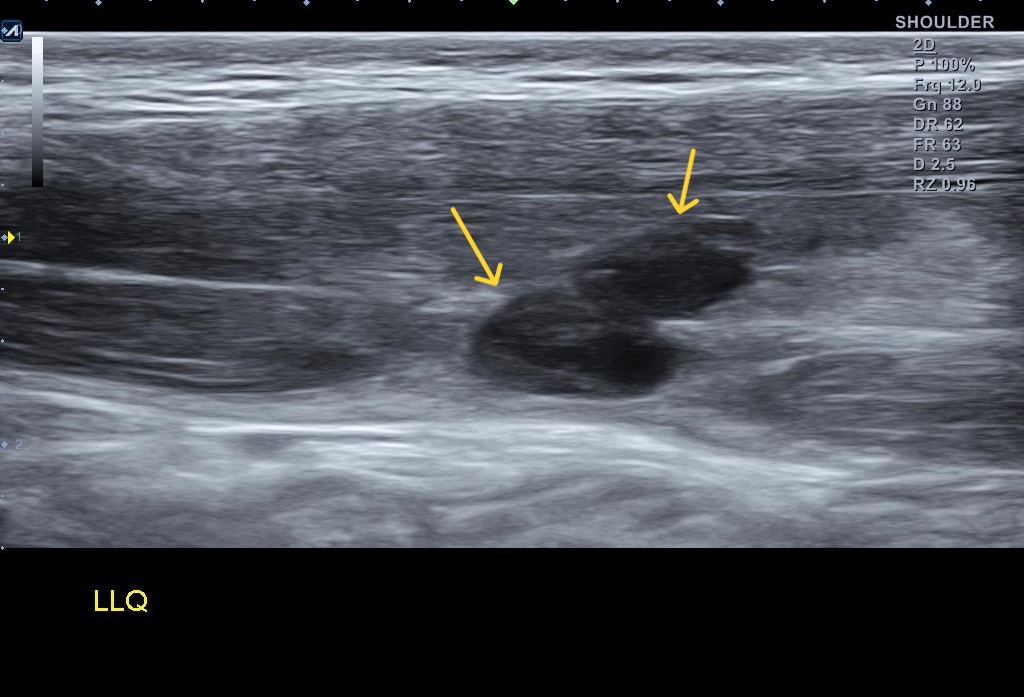

왜 슬픈 예감은 틀린적이 없을까요...일주일만에 다시 시행한 초음파 검사 상에서는... 복직근 파열이 훨씬 심해져 있었습니다.

나 : 초음파 한번 보세요.... 지난주에 비해 파열 크기가 훨씬 커졌어요... 근육에 빵꾸가 2개나 나버렸어요...

환자의 증상이 심해진만큼 복직근 파열도 훨씬 심해져 있었습니다. 보통 근육은 혈관 분포가 풍부해서 왠만큼 찢어져도 잘 붙는 조직입니다. 문제는 일상 생활에서는 근육 파열 통증이 금방 사라지기 때문에 완전히 회복하지 않은 상태에서 운동을 다시 하는 경우가 많고 그러다가 재파열이 흔하게 발생한다는 점입니다.

이런 경우에는 초음파 검사를 1~2주 간격으로 시행해서 근육 손상이 회복된것을 정확히 확인 후 운동을 복귀해야 부상의 재발을 막을 수 있습니다.